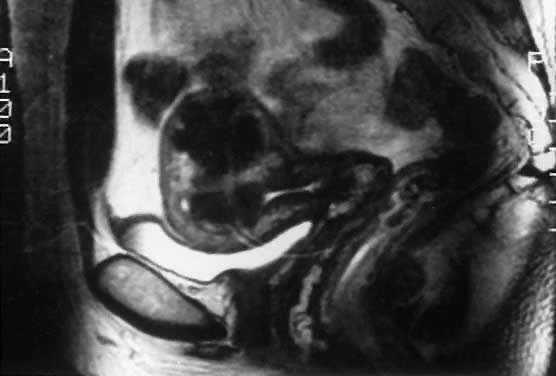

The typical problems presented by uterine leiomyomas have traditionally been evaluated by pelvic and abdominal examinations. Cantuaria and coworkers reported a strong correlation between bimanual examination and ultrasound examination with regard to determining the size of uterine myomas.10 The addition of ultrasonography (Fig. 3) and especially of magnetic resonance imaging (MRI) (Fig. 4) has increased the accuracy in the diagnosis and measurement of uterine leiomyomas. MRI often can differentiate adenomyosis from the leiomyoma. Radiologic studies are particularly important when the physical assessment is difficult, as in the case of morbid obesity, or when adnexal pathology cannot be excluded on physical examination. If there is any uncertainty about the diagnosis of uterine leiomyomas after radiologic studies, laparoscopy (Fig. 5), or laparotomy should be performed.

Fig. 4. Magnetic resonance image shows a myomatous uterus with an intramural and submucous myoma.